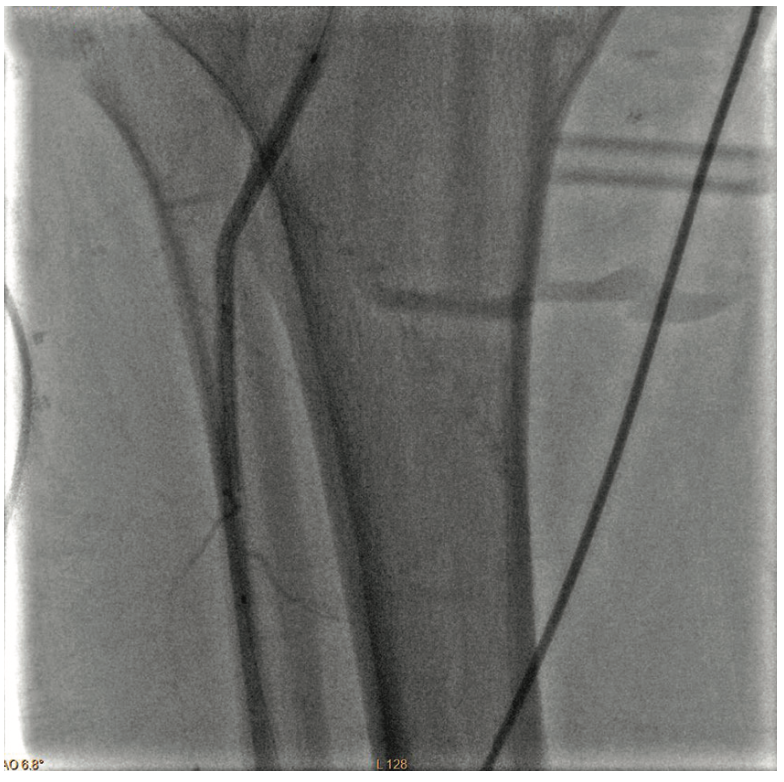

Inflow in the popliteal was optimized with plain balloon angioplasty (POBA) prior to addressing the BTK lesions (Figure 2). A 3 mm x 120 mm Serranator PTA Serration Balloon Catheter (Cagent Vascular) was utilized with serial overlapping inflations to treat the anterior tibial artery. The Serranator was used distal to proximal with max inflation at 12 atmospheres (atm) for two minutes (Figures 3-4). A 3 mm x 80 mm Serranator balloon was then used in a similar manner to treat the TPT, with a maximum inflation of 8 atm for two minutes. Following Serranator use, significant lumen gain and improved flow was observed, with 0% stenosis and no dissection, perforation, or recoil noted (Figure 5).

As previously planned, the patient returned two weeks after treatment of the right leg for treatment of his left leg. This procedure was markedly similar in both disease pattern and intervention to the previous one. Baseline angiography of the left leg also revealed patent iliac, common femoral and profunda arteries, moderate inflow disease of the SFA, and significant disease in the AT, TPT, and PT arteries (Figure 6):